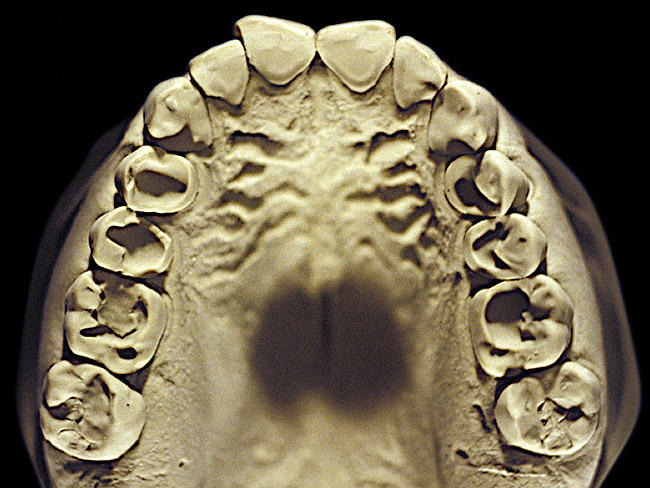

The patient shown in Figure 3 and Figure 4 exhibited severe NCLTS from bruxism. Examination of the casts indicated that the NCLTS was progressively greater toward the anterior teeth. Cupping and cratering was not present because there was no secondary cause. Figure 5 and Figure 6 detail another bruxism patient, but to a lesser degree and one with cupping/cratering caused by toothpaste. The cups or craters were not caused from bruxism because the teeth could not touch the bottom of the invaginations. In both featured patients, upon hand-articulating the casts, the NCLTS facets matched up and the diagnosis of bruxism was confirmed.

Figure 2  Advanced NCLTS from bruxism, mandibular arch.

Figure 2

Figure 4  Advanced NCLTS from bruxism, maxillary arch.

Figure 4